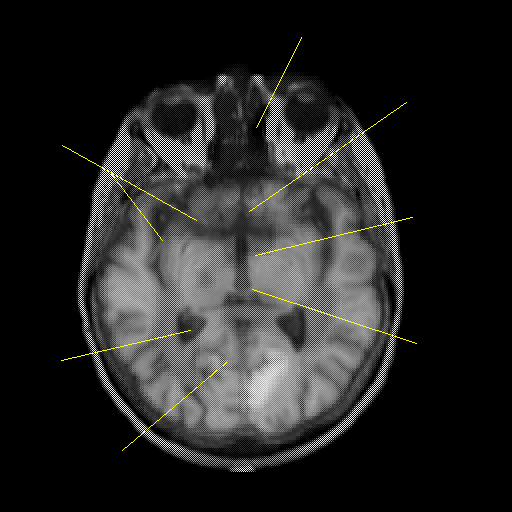

overlay: Slice 25

Slice 25

Pointers

Labeled